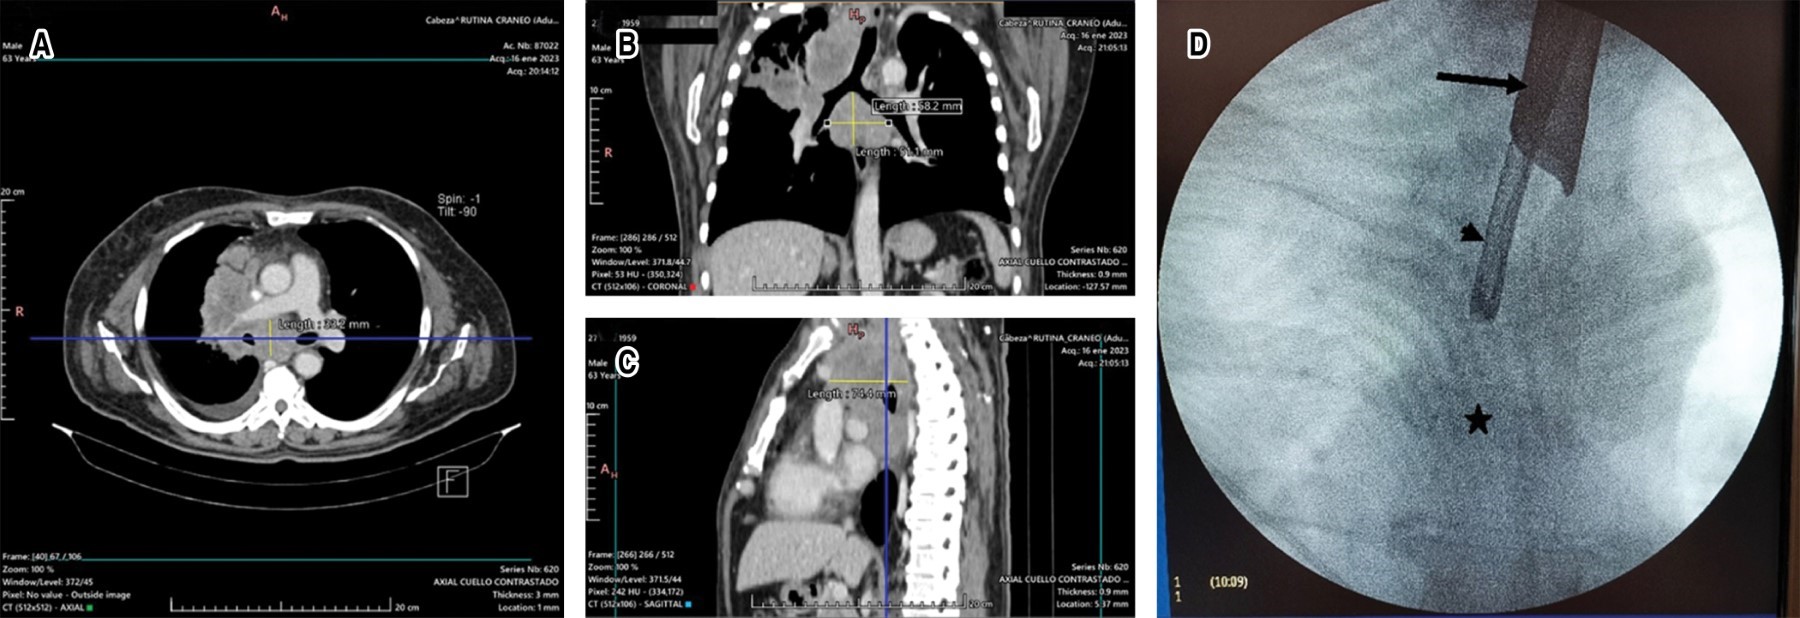

On admission, a simple and contrasted chest CT scan was performed; it showed a subcarinal mediastinal lesion measuring 58 × 51 × 74 mm, as well as a mass in the apical segment of the right upper lobe, a centrilobular micronodular pattern in the right upper and middle lobe, a subsolid nodule measuring 4. 3 × 5.2 mm in S7 and soft nodule of 5.4 × 5.1 mm in S8 of the right lower lobe, so it was decided to perform bronchoscopy with biopsy (Figure 1A-D). The procedure was performed under full sedation with the use of rigid tracheoscopy, with a rigid Hemer Richar Wolf® tracheoscope model with a diameter of 14 mm, and flexible bronchoscopy with a 5.9 mm diameter vi deobronchoscope with a 2.8 mm working channel Olympus Medical Systems®. With fluoroscopy support, a 21G eXcelonTM Boston Scientific® transbronchial aspiration needle was introduced for aspiration at the level of the main carina. Subsequently, Radial JawTM 4 Boston Scientific® forceps, 100 cm in length, with 1.8 mm diameter forceps were introduced with a double purpose: first, to collect tissue sample and, second, to increase the diameter of the orifice; finally, through the same puncture site, a flexible cryoprobe of 1. 9 mm × 900 mm Erbe® flexible cryoprobe connected to the ERBECRYO 2® cryosurgery unit, with a freezing time of four seconds, was thawed in warm saline; a total of three samples were collected, with no post-procedure bleeding. Two tissue samples, each measuring 0.1 × 0.1 cm, were obtained using forceps and three samples were obtained by cryobiopsy, together measuring 0.6 × 0.3 × 0.2 cm, ideal for immunohistochemistry and mutational studies in pathology.